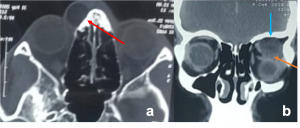

Granulomatosis with Polyangiitis. Non-contrast axial CT images in soft tissue window showing left orbital large infiltrative extra- and intra-conal soft tissue masses that mould to the orbital contour associated with proptosis of the globe. Ipsilateral maxillary sinus in the same case showed pansinusitis with medial wall sclerotic thickening. | |